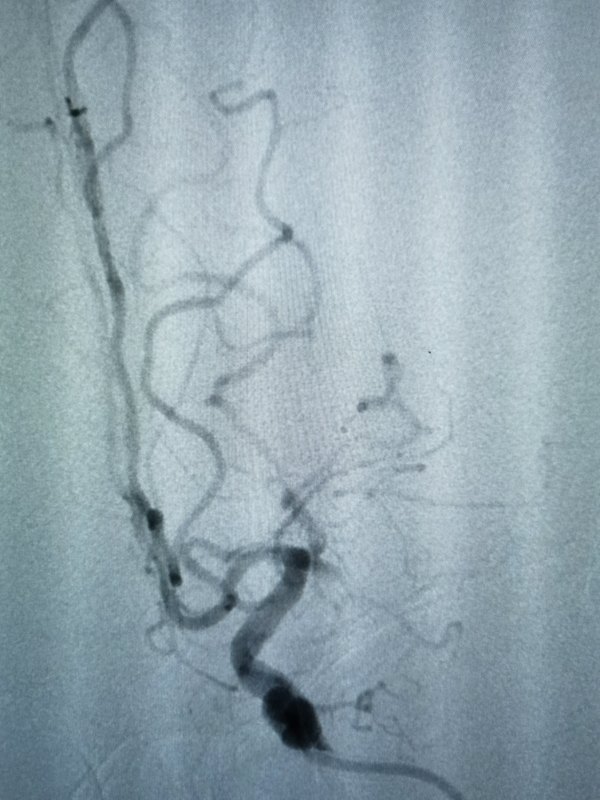

身體有有問題抗過過年都開始檢查身體看病了,發(fā)揮傳統(tǒng)優(yōu)勢(shì)介入技術(shù)(腦動(dòng)脈瘤支架輔助彈簧圈栓塞術(shù)),開發(fā)介入新技術(shù)(顱內(nèi)動(dòng)脈狹窄藥物球囊成形術(shù)-介入無植入),服務(wù)患者,做到安全,省錢,可靠,長期效果好[福]病例一病例二藥物球囊血管內(nèi)介入成形治療顱內(nèi)動(dòng)脈狹窄,無需植入支架,遠(yuǎn)期效果好

急性腦卒中發(fā)病急,強(qiáng)求時(shí)間更急,今日院內(nèi)心外科一患者發(fā)病,房顫導(dǎo)致左側(cè)大腦中動(dòng)脈閉塞,急性腦卒中。支架取栓一把通,臨床試驗(yàn)還免費(fèi)?,低費(fèi)用解決大問題。